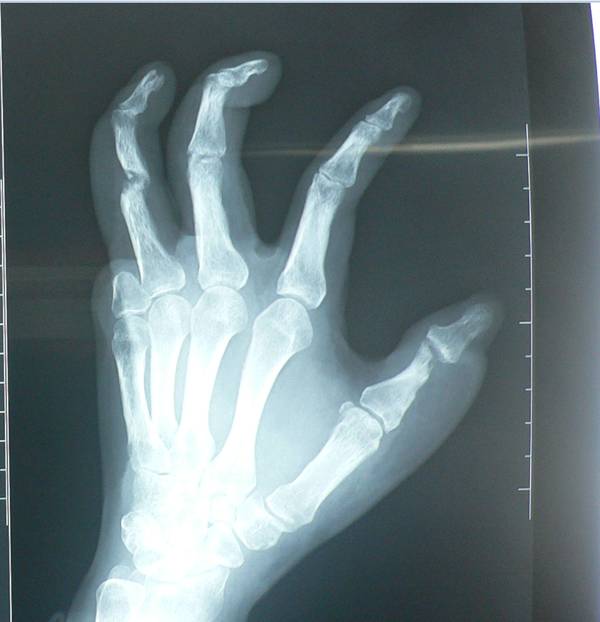

给你看两张片子,你就明白为什么不做肌腱移植了。拇指、示指、中指的关节都已经破坏吸收了。

伤后8个月